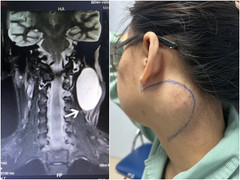

Bệnh viện Chợ Rẫy (TP.HCM) vừa phẫu thuật thành công khối u sợi thần kinh bẩm sinh hiếm gặp, nặng gần 1kg, gây biến dạng mặt và tai cho bệnh nhân.